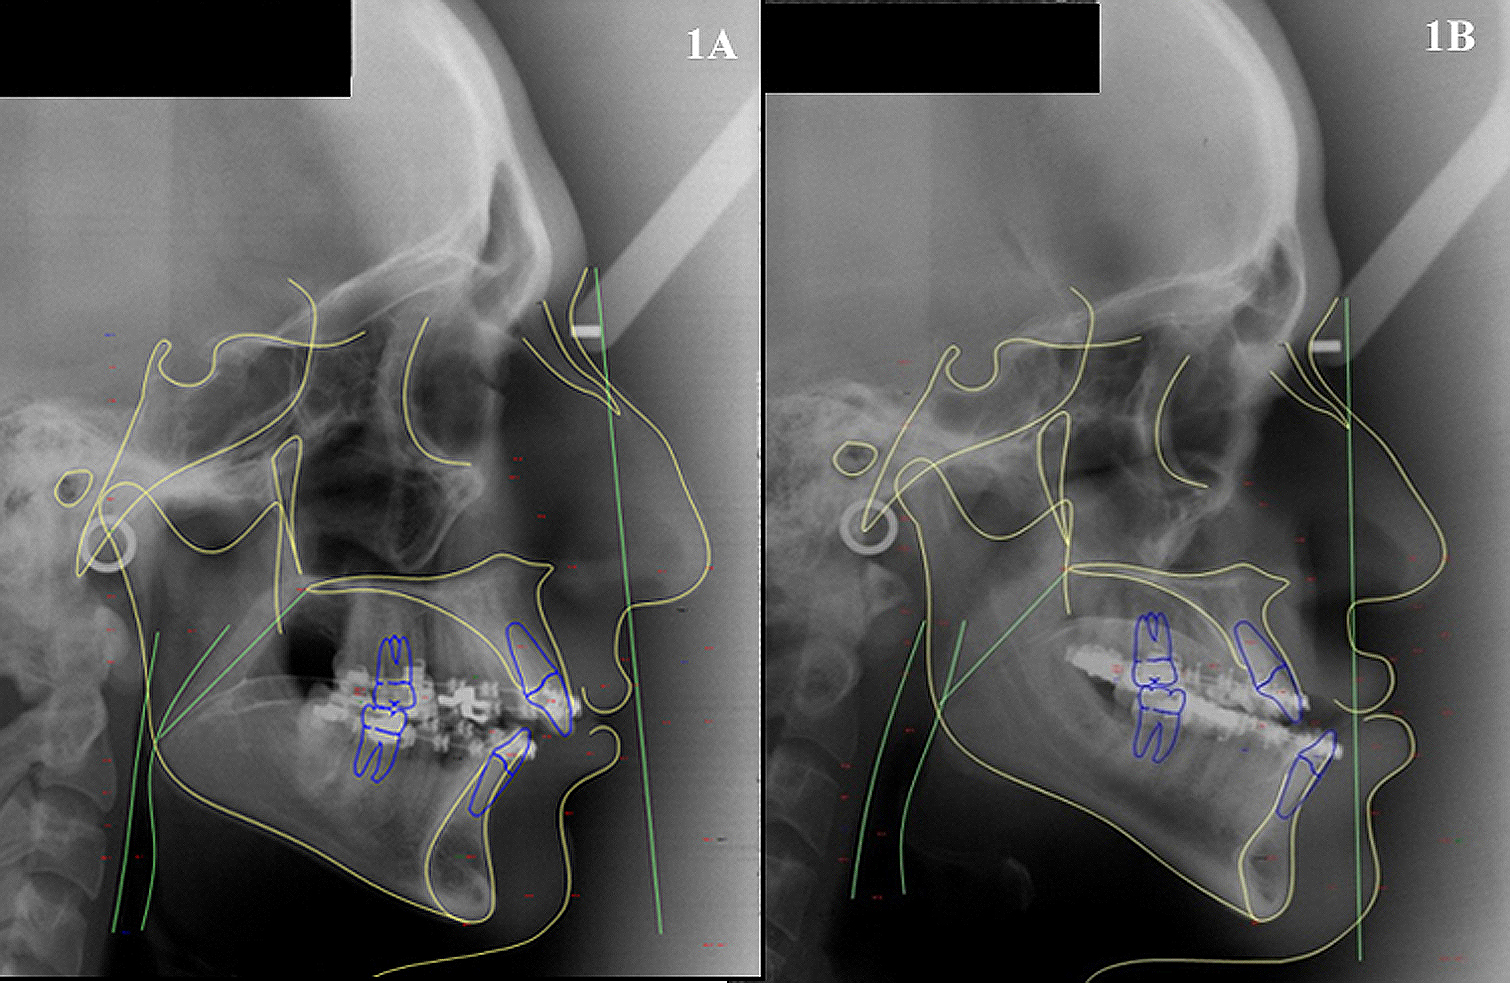

Orthognathic surgery is widely used in the treatment of dento-maxillofacial deformities, which changes both the facial appearance and the pharyngeal airway space. The aim of this study was to evaluate cephalometric changes in the pharyngeal airway space before and after orthognathic surgery in patients with Class II and Class III malocclusions. The sample consisted of 38 lateral cephalograms, 17 of patients with Class II who had undergone mandibular advancement, and 21 of patients with Class III who had undergone mandibular setback. Cephalometric analysis of Arnett-Gunson FAB Surgery using Dolphin Imaging 11.5 evaluated point B’ and Pog’. Statistical analysis used Paired t-test at 5% significance level. The increase in the means of point B’ and Pog’ after mandibular advancement was not statistical. Similarly, the means of point B’ and Pog’ did not differ after mandibular setback. Thus, the pharyngeal airway space at the level of B’ and Pog’ kept constant pre and post orthognathic surgery for both Class II and Class III.